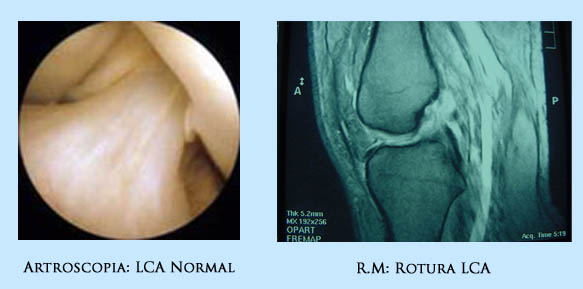

La rotura del LCA se debe confirmar con una Exploración Clínica realizando las maniobras que ponen de manifiesto su rotura y se debe de confirmar con pruebas complementarias, siendo la mas útil la Resonancia Magnética, que además de confirmar la rotura del LCA, nos informa de las lesiones asociadas que pudieran tener (lesiones de los meniscos y del cartílago), útil para la programación y estrategia quirúrgica.